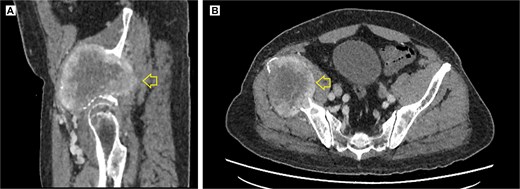

The pelvic radiograph showed a lytic lesion measuring 8 × 8 cm on the outer edge of the right iliac bone (Fig. 1), which was initially considered as a giant cell tumor. Given these findings, a computed tomography (CT) scan of the thorax, abdomen, and pelvis was requested to evaluate possible tumor dissemination. The CT scan revealed a heterogeneous expansive mass measuring 113 × 96 × 100 mm with destruction and remodelation of the right iliac bone (Fig. 2), a 45 × 38 mm mass in the right chest wall with heterogeneous contrast (Fig. 3), three pulmonary nodules in the left lower lobe (5–12 mm) (Fig. 4A) and multiple hypo- and isodense hepatic lesions (10–28 mm in both hepatic lobes) (Fig. 4B). That same month, two biopsies were performed. The first, from the right chest lesion, showed positivity for CD34, BCL-2, and STAT6 in the immunohistochemical study, confirming the presence of an SFT. The second, from the right iliac crest lesion, showed a spindle-cell sarcoma with bone invasion, with immunohistochemistry positive for CD34 and vimentin, a Ki-67 index of 10%, and negative for cytokeratins. This biopsy was processed in a public hospital pathology laboratory, where reagents for BCL-2 and STAT6 were not available at the time of analysis. Based on the histologic appearance, partial immunophenotype, and clinical context, the iliac lesion was considered highly suggestive of metastasis from the chest wall tumor. However, due to the patient’s rapid clinical deterioration and subsequent death, confirmatory testing by STAT6 immunostaining could not be performed.

Contrast-enhanced pelvic CT scan. (A) Sagittal view of tumor in iliac crest. (B) Axial view of the iliac crest. Expansile soft tissue mass (arrow) of 113 × 96 × 100 mm, with central necrotic degeneration and heterogeneous contrast enhancement but predominantly peripheral.